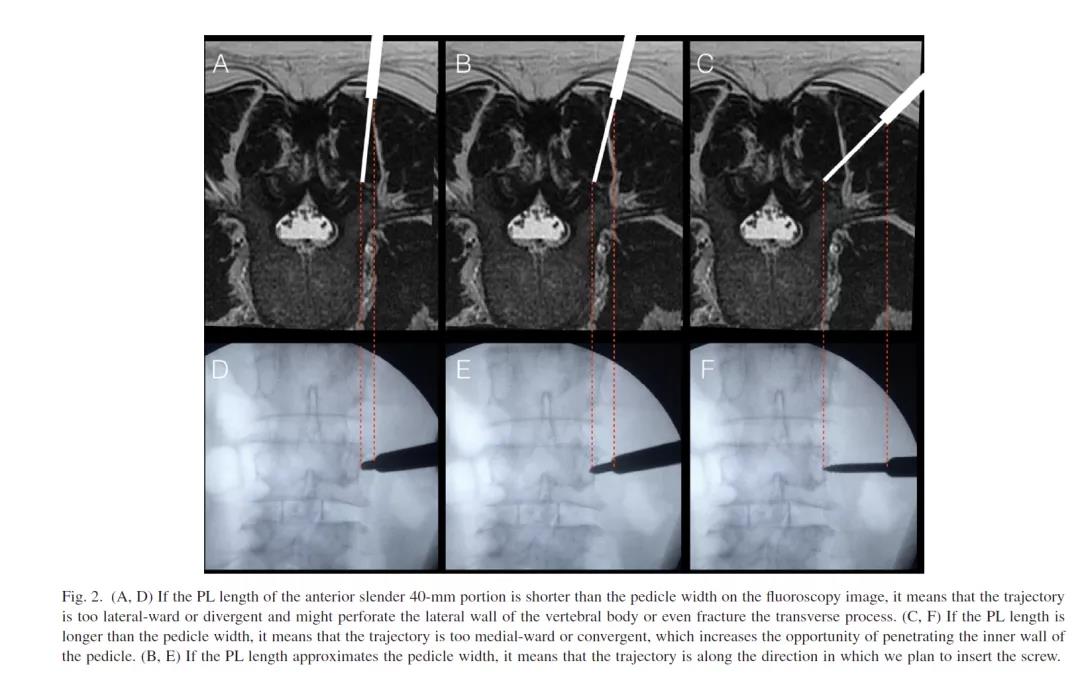

原理:单一斜位其实是椎弓根的轴位,在此位置椎弓根影像成为最大的圆。如果置钉过程中,钉头始终在这个圆内,表明椎弓根钉没有穿破内外上下皮质。方法:①调整C臂头尾倾位置,使终板影重叠成一直线。小技巧,此时C臂头尾倾的角度就是穿刺针头尾倾的角度。②调整C臂内外倾位置,椎弓根圆形影像最大化的位置就是椎弓根的轴位,保持此位置。小技巧,此时C臂内外倾的角度就是穿刺针头内外倾的角度。③进钉点位于圆圈内(最好位于圆中心)。④一直朝圆心方向进入穿刺针,进入椎弓根钉的长度后(腰椎45cm、胸椎35cm、颈椎25cm),透视穿刺针尖没有超过圆圈。⑤另外,掌握了原理后,这种经皮的方法在开放也同样适用。